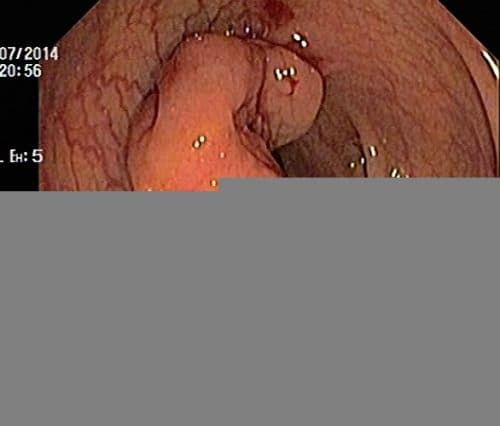

Ung thư đại tràng cũng có thể phát hiện được nhờ nội soi đại tràng

Khám nội soi đại tràng là một phương pháp thăm khám giúp phát hiện ra những bệnh lý tiềm ẩn trong đại tràng như viêm loét, polyp hoặc khối u. Với kết quả nội soi đại tràng của bố bạn, được chẩn đoán có khối u ở đại tràng khi muốn điều trị đạt hiệu quả cao cần xác định rõ vị trí, kích thước khối u cũng như giai đoạn bệnh cụ thể.

Ngoài ra, người bệnh có thể cần phải nội soi đại tràng lại để sinh thiết khối u nhằm xác định mức độ và tình trạng bệnh cụ thể. Khi đánh giá được sức khỏe tổng thể của người bệnh, bác sĩ sẽ tư vấn phương pháp chữa trị phù hợp.